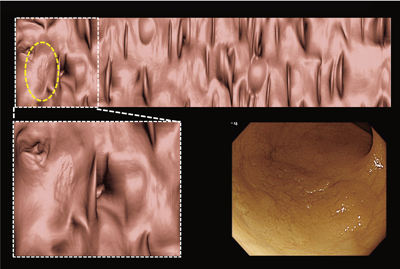

【大放出セール】 Amazon.co.jp: 大腸CTテキスト: 原理・特性の基礎知識から現場で 語学+参考書の詳細情報

Amazon.co.jp: 大腸CTテキスト: 原理・特性の基礎知識から現場で。大腸CT検査~実務・症例・基礎知識~: イチから学ぶ! | 東海。大腸CT検査 | 医療法人 山下病院|愛知県一宮市の消化器内科。 現在、1名がこの商品を検討中です

撮影から読影までを網羅した東芝の大腸CT技術について - 東芝

撮影から読影までを網羅した東芝の大腸CT技術について - 東芝

大腸CTテキスト:原理・特性の基礎知識から現場で使えるセッティング,読影法まで消化管先進画像診断研究会

大腸CTテキスト:原理・特性の基礎知識から現場で使えるセッティング,読影法まで消化管先進画像診断研究会